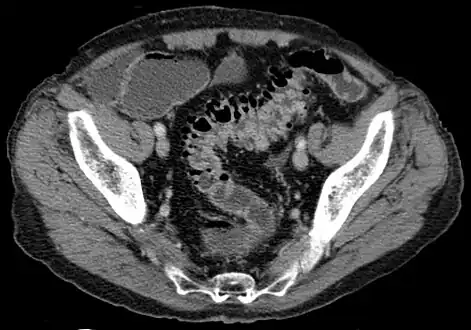

CT scan showing extensive diverticulosis of the sigmoid colon

Diverticular disease

Diverticulosis is defined by the presence of multiple pouches (diverticula) in the colon.[22] In people without symptoms, these are usually found incidentally during other investigations.

- Contrast CT is the investigation of choice in acute episodes of diverticulitis and where complications exist.